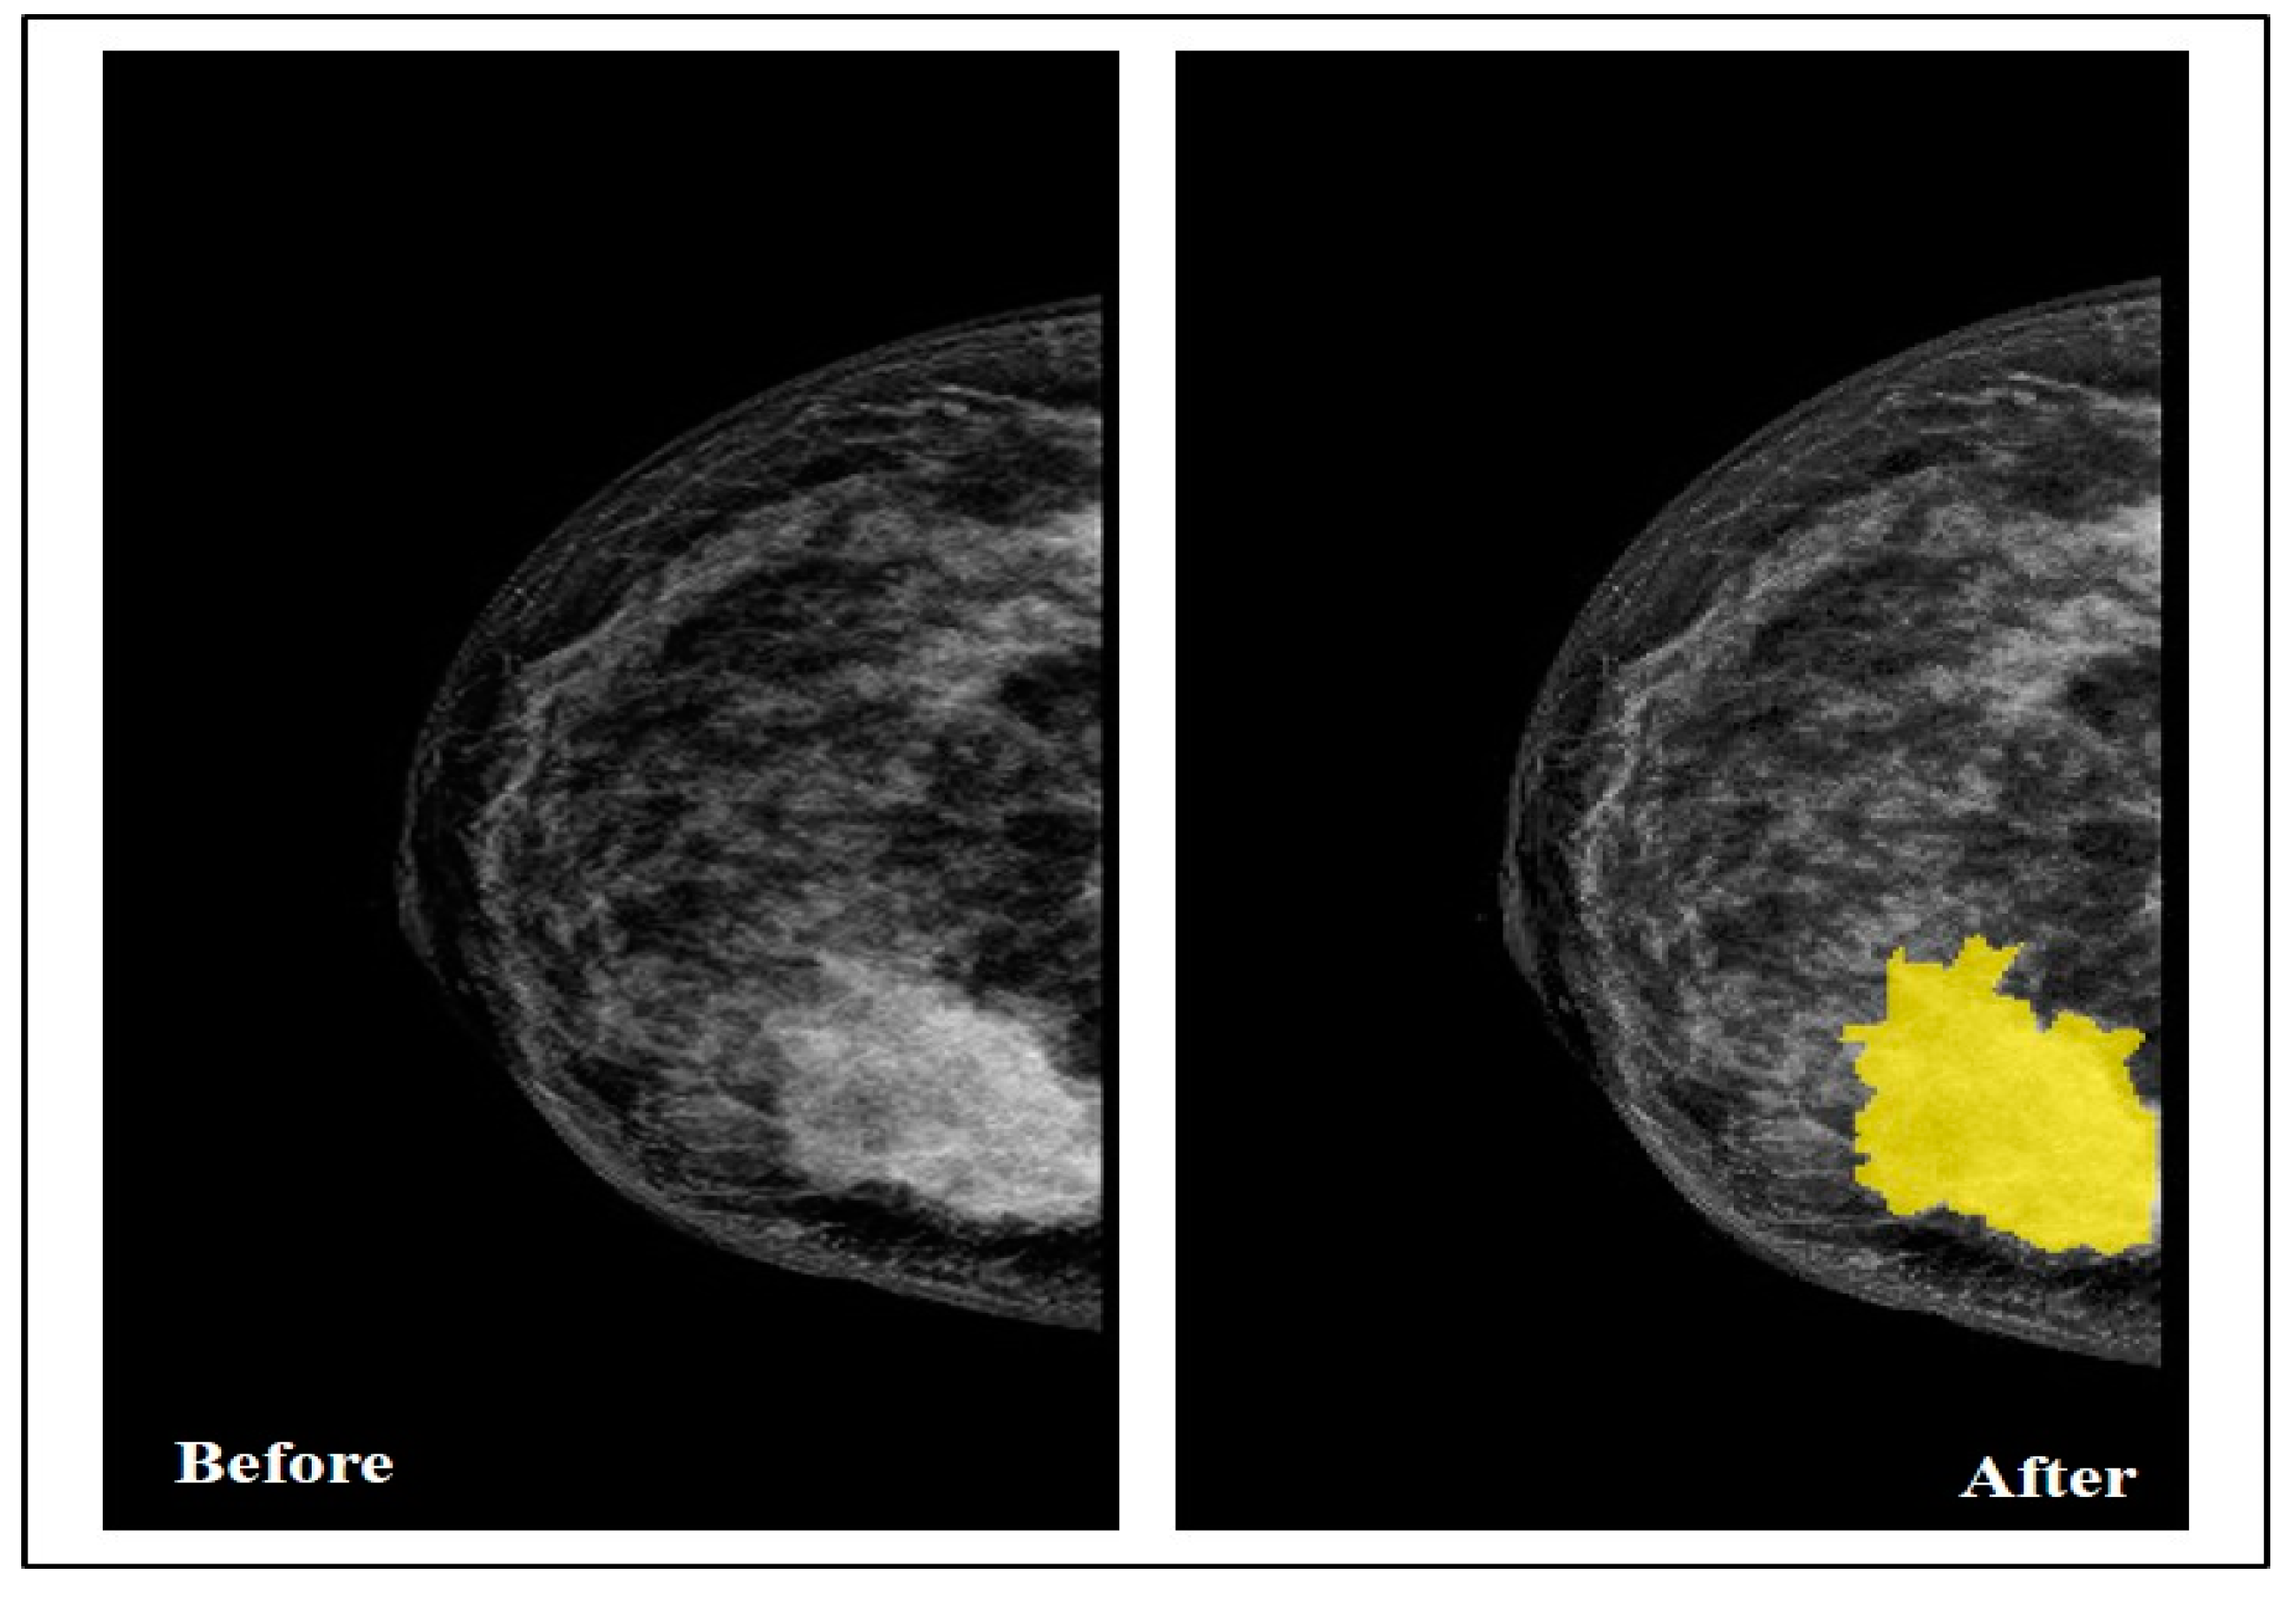

By collaborating with the radiologist, the Segmenter tool in MATLAB was used in this step to manually annotate the tumor region by drawing its border in all the selected images, as seen in Figure 3.

After drawing the tumor border, the segmented tumor area (ROI) was converted to binary and masked images, as seen in Figure 4. The image conversion was done using the function generator by the Segmenter tool. The masked image represents only the ROI and it was extracted from the breast without its background. The binary and masked images were exported to use in the features extraction step.

Figure 3. Breast before and after drawing the tumor border.